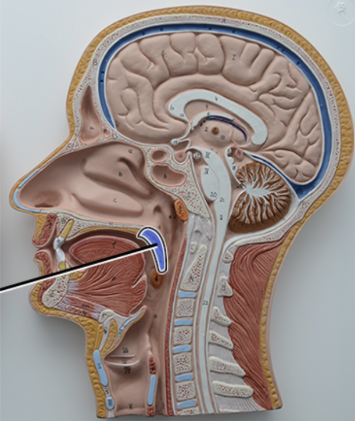

What structure is this?

Soft Palate